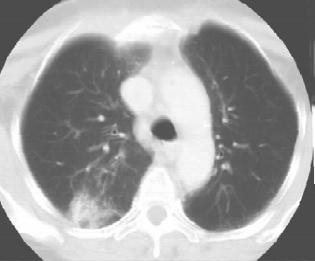

2.其他辅助检查 X线表现多数于停止放射治疗1~3个月后出现。急性期在照射肺野出现片状或融合成大片的、致密的模糊阴影,照射范围呈毛玻璃样表现,其间隐约可见网状阴影,与支气管肺炎或肺水肿极相似;慢性期产生肺纤维化,呈网状、条索状或团块状收缩阴影,主要分布于肺门或纵隔两侧及其他放射肺野。由于肺纤维收缩,气管、心脏移向病侧,同侧膈膜抬高,正常肺组织产生代偿性肺气肿。发生肺动脉高压时,表现为右肺下动脉横径增厚、肺动脉段突出或右心肥大。常伴胸膜腔积液征,偶见自发性气胸。见图1-5。

图1-5 女,58岁,右乳癌术后,放射性肺炎